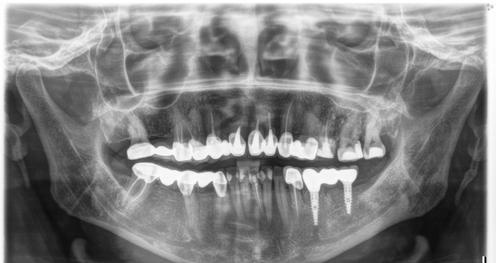

1. ábra: A 12. fog - a röntgenfelvételen nagyméretű periapikális elváltozás látható. A tünetmentes fogat ISO 25/.06 TF Adaptive reszelővel (Kerr Dental) preparáltuk. – 2. ábra: A 12. fog gyökércsatornájának tömését ásványi trioxid aggregátummal (ENDOSEAL MTA, Maruchi) végeztük. Figyeljük meg az apikális elágazás lezárását, ami az apikális terminus hatékony tisztítása és dekontaminálása miatt lehetséges. A gyógyulás 12 hónap elteltével csaknem teljes volt. – 3. ábra: 33. fog - a páciensnél egy bukkális sinus traktus volt látható, amely röntgenfelvételen a 32. és a 33. fog közötti területnek felelt meg. A CBCT és a röntgenfelvétel nagyméretű periradikuláris elváltozást mutatott, különösen a disztális oldalon. A preparálást 20/,07v ProTaper Gold (F1; Dentsply Sirona) készülékkel végeztük. – 4. ábra: A 33. fog gyökércsatorna obturációját sealer és hordozó alapú guttapercha (AH Plus és Thermafil, Dentsply Sirona) segítségével végeztük. A hat hónappal a műtét után végzett röntgenellenőrzés azt mutatta, hogy több oldalsó csatorna feltöltődött, és a gyógyulási folyamat folyamatban van.

keletkeznek [25-29]. A másodlagos kavitációs buborékok összeomlásuk során a csatornafalak közvetlen közelében vannak, nyírófeszültséget és örvényes áramlásokat generálva, amelyek képesek eltávolítani a törmeléket, a kenetréteget és a biofilmet a gyökércsatorna felszínéről, valamint a fel nem fedezett és műszerrel nem rendelkező anatómiai területekről, például az isztmuszokból, az oldalsó csatornákból, a hurkokból és a ramifikációkból, ezáltal tovább fokozva a tisztítási és dekontaminációs mechanizmust (1-4. ábra). A gyökércsatorna mentén létrejövő fokozott nyomás következésképpen az irrigálószereknek a dentinális tubulusokba való behatolásának mélységét is növeli [25-28].